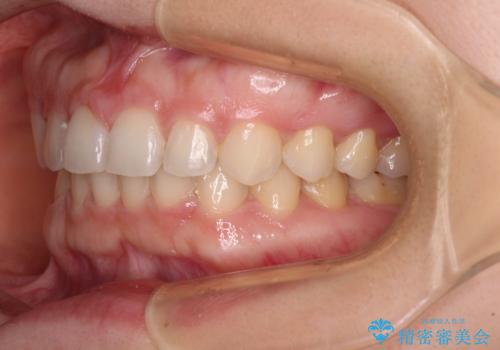

- 前歯の隙間やクロスバイトを気にして来院された患者様です。

結婚式の予定があり、可能であれば結婚式までに治療を終えたいとのことで、短期間で治療をおける可能性の高いワイヤー装置にて矯正治療を行うこととしました。

ギリギリとなりましたが、結婚式直前にワイヤー装置を外すことができました。

ワイヤー装置除去後に細かい部分を短期間のマウスピース矯正にて仕上げました。